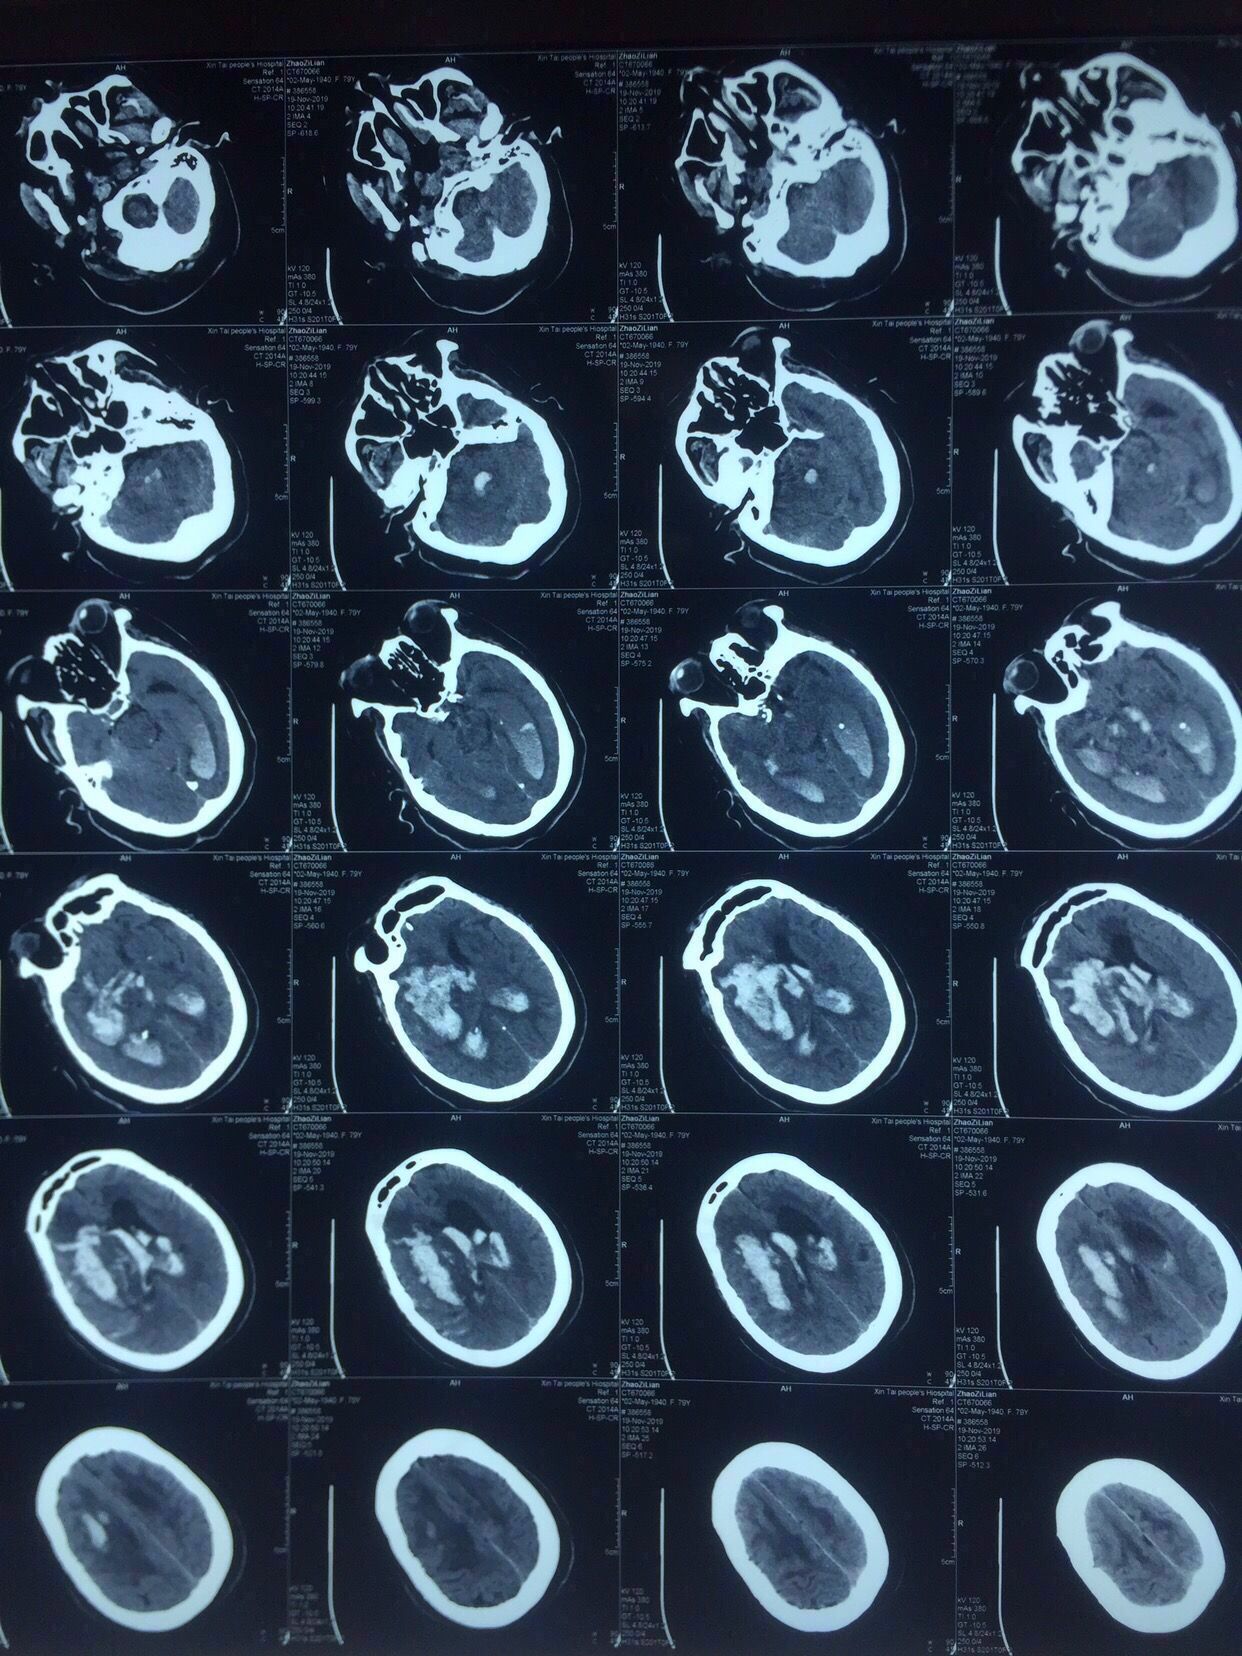

认真阅片可知,血肿最大层面就是脑室额角层面,EVD的靶点就是额角室间孔位置,我们把血肿靶点也定在这一层,右侧血肿内,右侧额角室间孔位置偏右,如图↑↑

经kocher点穿刺定位画线↑↑

中线旁开2.5㎝平行矢状线穿刺右侧血肿;偏内穿左侧脑室

中线旁开2.5㎝可以让穿刺管几乎游走在所有的血肿层面内↓↓↓↓↓↓4张照片